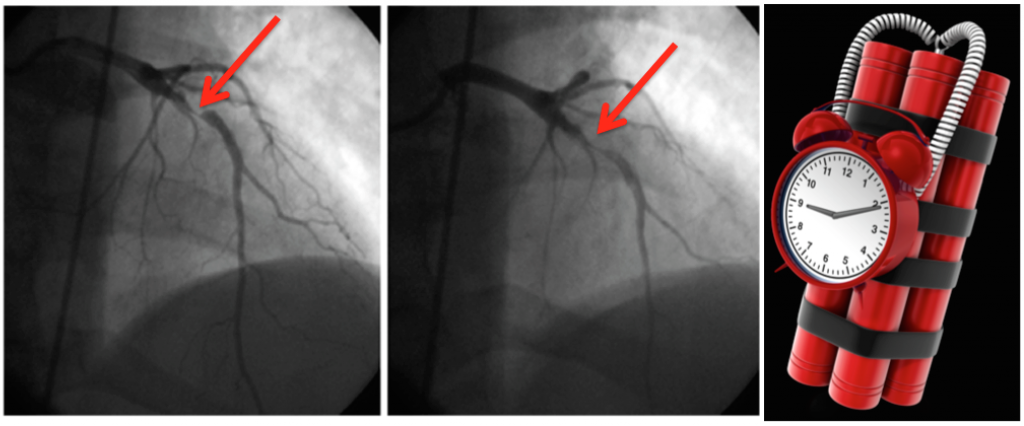

Wellens Syndrome atau Wellens Sign merupakan manifestasi EKG dari Critical Proximal Left Anterior Descendeing Artery Stenosis pada pasien dengan unstable angina

Wellens Syndrome dalam EKG merupakan pola T- Inverted yang dalam atau Bifasik pada lead V2 dan V3 yang mempunyai spesifitas tinggi dalam stenosis dari proximal LAD artery

Karena Stenosis yang berat, pasien biasanya membutuhkan terapi invasif